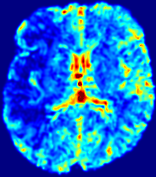

LesionRefer to captionRefer to captionRefer to captionRefer to captionRefer to captionRefer to caption𝐕rgbsubscript𝐕𝑟𝑔𝑏{\bf{V}}_{rgb}Refer to captionRefer to captionRefer to captionRefer to captionRefer to captionRefer to caption𝐕2subscriptnorm𝐕2{\|\bf{V}}\|_{2}Refer to captionRefer to captionRefer to captionRefer to captionRefer to captionRefer to captionRefer to caption3.53.53.52.82.82.82.12.12.11.41.41.40.70.70.70.00.00.0(mm/s)𝑚𝑚𝑠(mm/s)D𝐷DRefer to captionRefer to captionRefer to captionRefer to captionRefer to captionRefer to captionRefer to caption0.0200.0200.0200.0160.0160.0160.0120.0120.0120.0080.0080.0080.0040.0040.0040.0000.0000.000(mm2/s)𝑚superscript𝑚2𝑠(mm^{2}/s)Slice #1Slice #2Slice #3Slice #4Slice #5Slice #6

Figure 3: PIANO feature maps for one stroke patient, where the lesion is located in the left hemisphere. Top row: segmented stroke lesion region (white) on different slices, obtained from ISLES 2017. The corresponding slices for the PIANO feature maps are shown in the following rows.

For a better insight into an estimated velocity field 𝐕𝐕{\bf{V}} and diffusion field 𝐃𝐃{\bf{D}}, we compute the following maps: (1) 𝐕rgbsubscript𝐕𝑟𝑔𝑏{\bf{V}}_{rgb}: Color-coded orientation map of 𝐕=(Vx,Vy,Vz)T𝐕superscriptsuperscript𝑉𝑥superscript𝑉𝑦superscript𝑉𝑧𝑇{\bf{V}}=(V^{x},V^{y},V^{z})^{T}, obtained by normalizing 𝐕𝐕{\bf{V}} to unit length and mapping its 3 components to red, green, blue respectively; (2) 𝐕2subscriptnorm𝐕2\|{\bf{V}}\|_{2}: 222 norm of 𝐕𝐕{\bf{V}}; (3) D𝐷D: scalar field in Eq. 5.

Fig. 3 and Fig. 4 show the PIANO feature maps estimated from two ISLES 2017 patients: all are highly consistent with the lesion in both cases. Details of the blood flow trajectories are revealed in 𝐕rgbsubscript𝐕𝑟𝑔𝑏{\bf{V}}_{rgb} by the ridged patterns and the sharp changes of colors in the unaffected (right) hemisphere, while the flat patterns appearing within the lesion provide little directional information about the velocity and indicate low velocity magnitudes. Velocity magnitudes are more directly visualized via 𝐕2subscriptnorm𝐕2\|{\bf{V}}\|_{2}, from which one can easily locate the lesion where 𝐕2subscriptnorm𝐕2\|{\bf{V}}\|_{2} is low. D𝐷D also indicates lower diffusion values in the lesion, though with less contrast potentially due to the fact that it captures the accumulated effect of CA diffusion at the voxel-level.